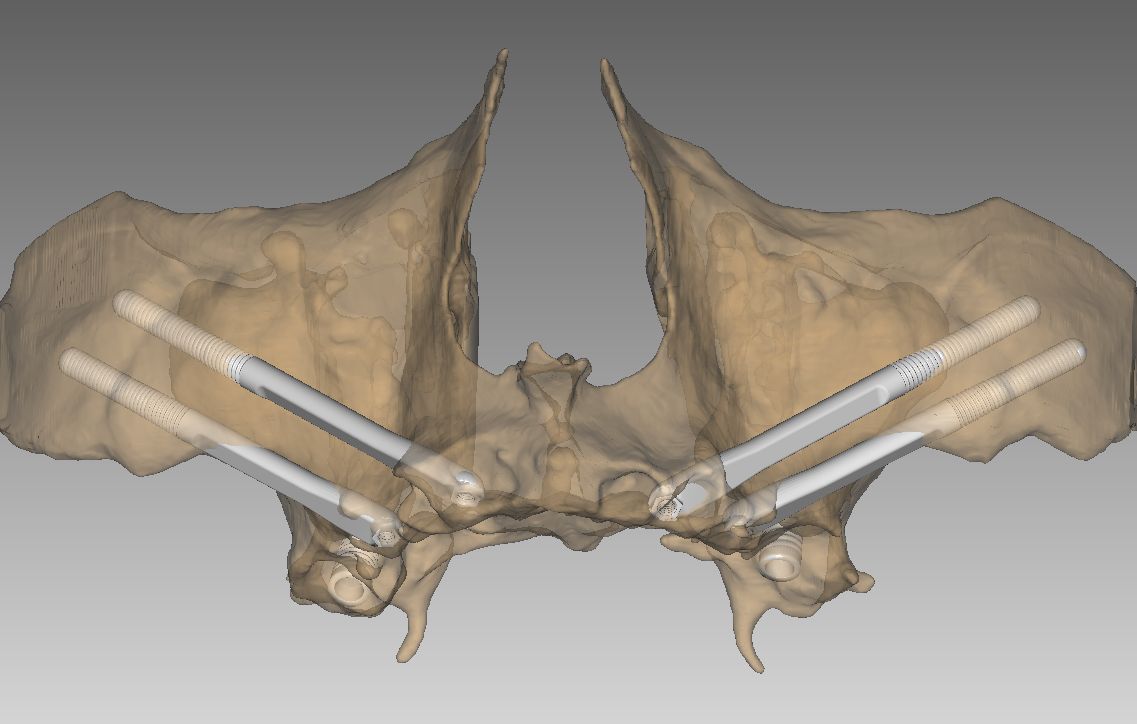

1. Implantes Cigomáticos

Son implantes más largos que se fijan en el cuerpo del hueso cigomático (pómulo). Son la «regla de oro» para tratar maxilares totalmente atróficos. Permiten colocar una arcada completa de dientes fijos sin necesidad de realizar injertos de cadera o calota craneal, reduciendo drásticamente la morbilidad del paciente.

Se anclan en estructuras del esqueleto facial como el hueso cigomático (pómulo), la apófisis pterigoidea o la región transnasal. Al fijarse en este «hueso basal» o cortical, garantizamos una estabilidad mecánica superior desde el primer día.

Cada paciente presenta una anatomía única. Por ello, en nuestra clínica de Soria, realizamos un estudio tridimensional para determinar qué combinación de implantes es la adecuada:

- Planificación digital y cirugía guiada para máxima precisión.